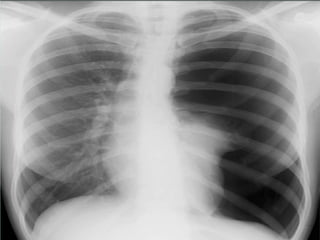

Tension pneumothorax

High pressure pneumothorax causing

cardiovascular compromised status

* chest injury

* dyspnea & tachypnea

* distended neck vein

* deviated trachea

* hypotension

* tympanic on percussion

* absent breath sound